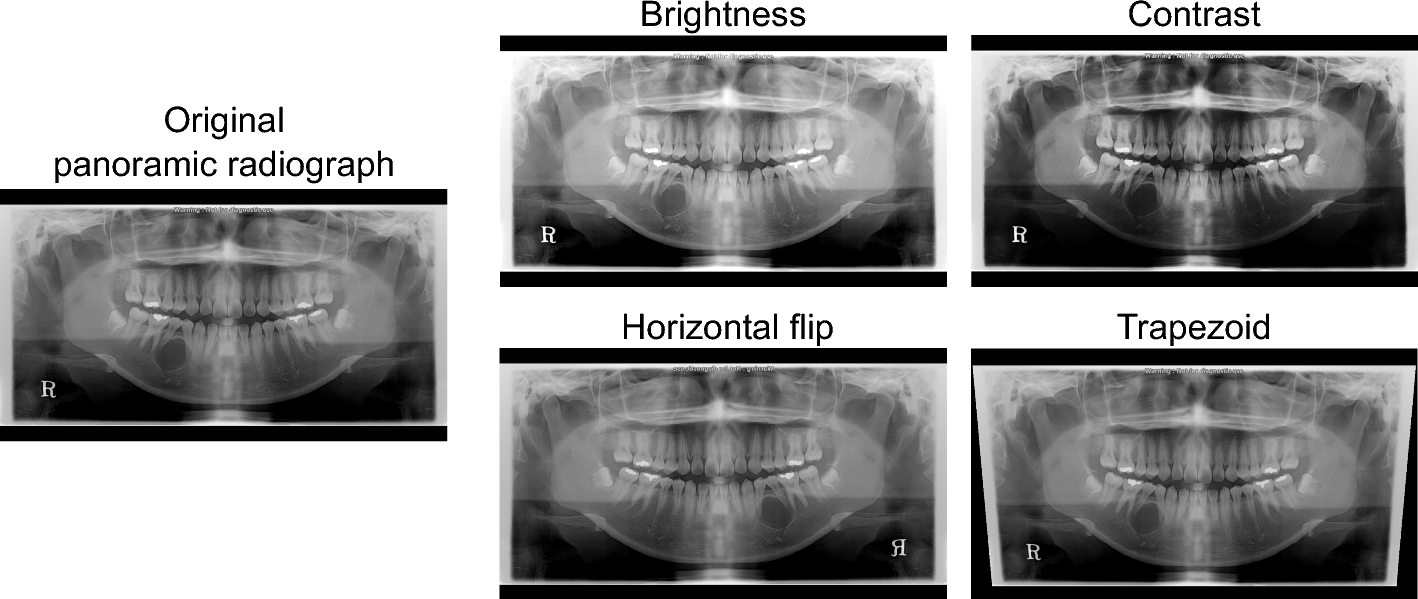

Data augmentation methods.